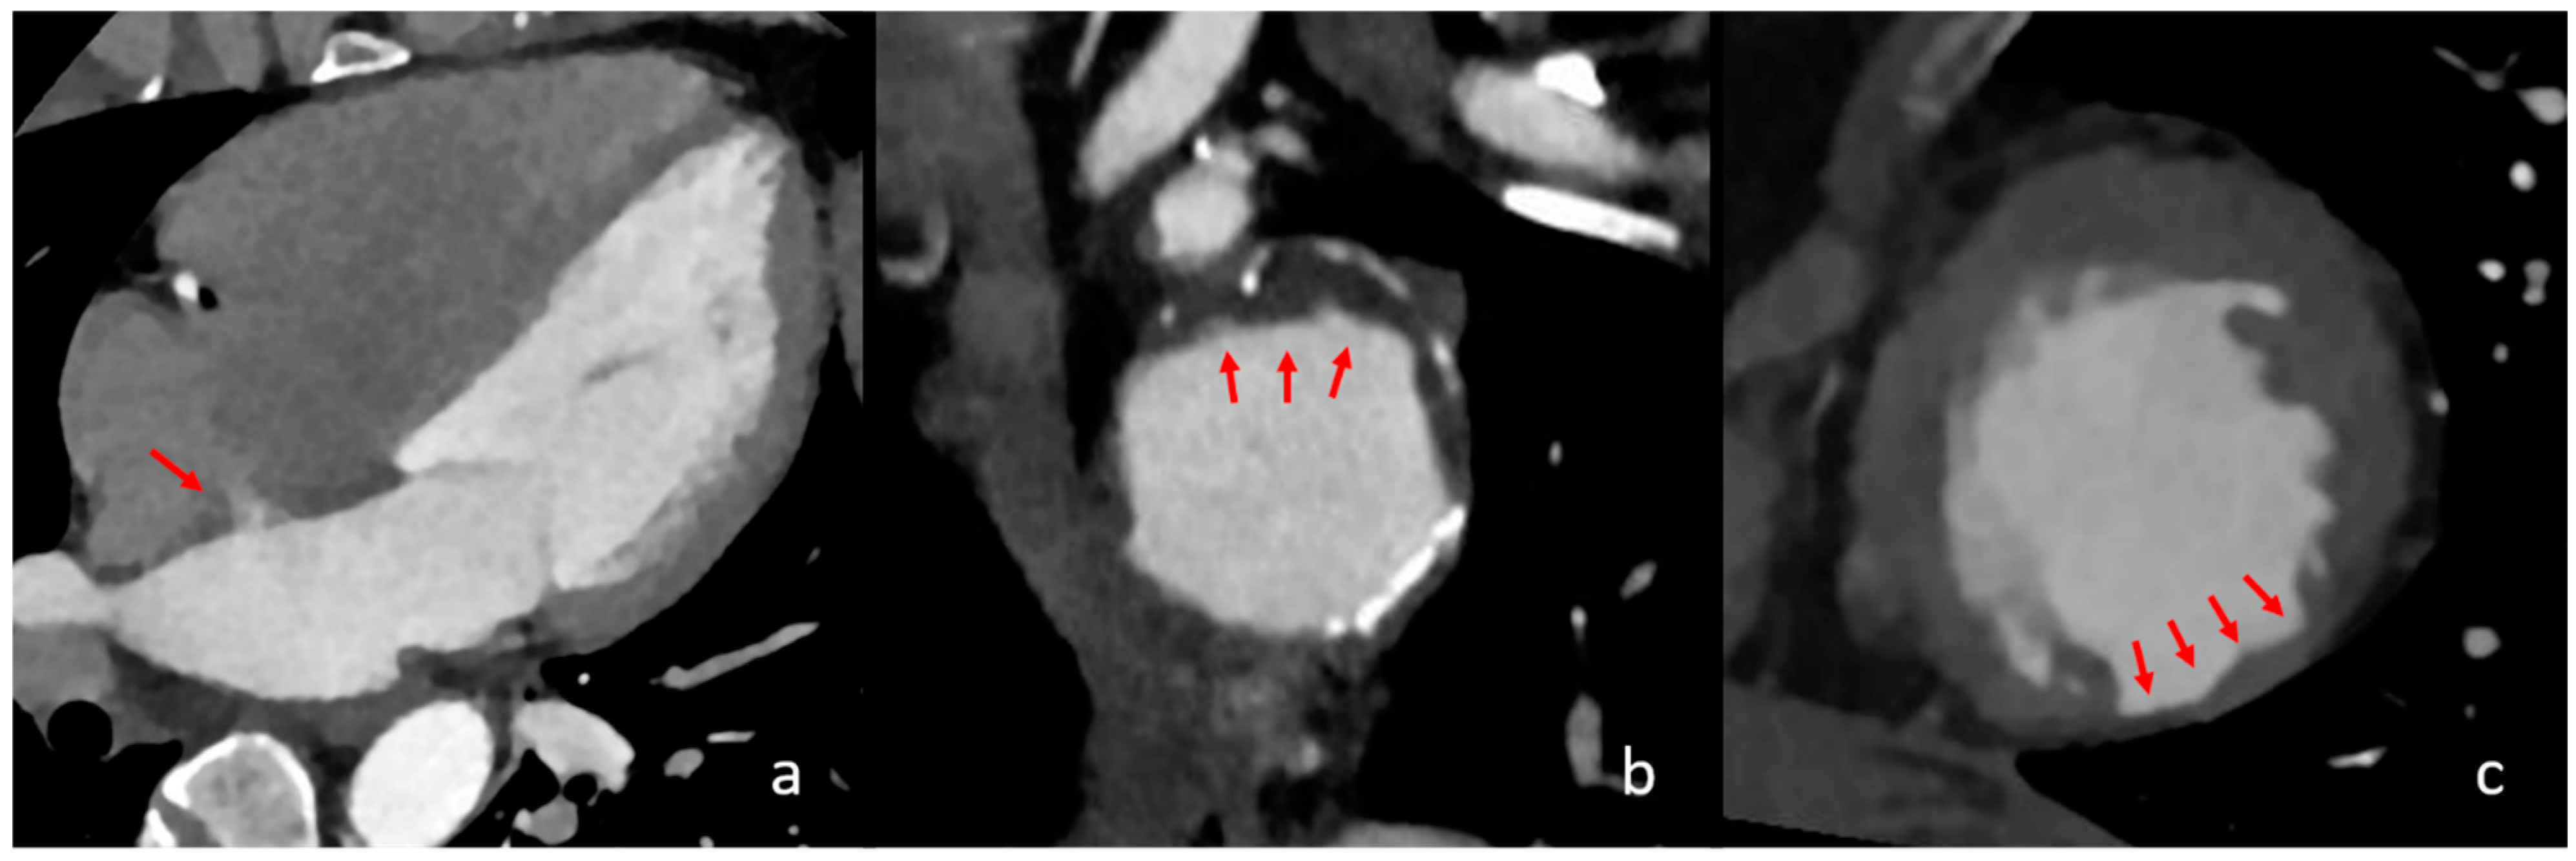

Figure 2.

Different cardiac imaging findings with significant influence on a cardioembolic stroke aetiology. In the above images, different relevant cardiac findings are depicted that are associated with a cardioembolic stroke. In image (a), a four-chamber view is seen with contrast in the left atrium, left ventricle and aorta. The red arrow shows a persistent intra-atrial shunt, seen as contrast jet from the left to the right atrium. In image (b), reconstructed images of the aortic arch in the axial orientation show partially exulcerated plaques at the greater curvature of the aortic arch, marked with red arrows. In image (c), axial orientation slices of the left ventricle depict post-ischaemic myocardial scarring as the circumscribed thinning of the left ventricular myocardium, which is marked with red arrows.

4.3. Visible Interatrial Shunt and PFO

The presence of visible interatrial shunting was associated with a 30.1-fold increase in the likelihood of a cardioembolic stroke (Figure 2). A PFO with a right-to-left shunt is conventionally considered a low-risk CES and is mainly discussed in the context of ESUS, where it is considered a high-risk source, especially in young patients [29]. Its prevalence in the general population is estimated at 18–34% [30,31]. While the reference standard for PFO detection is TEE, cCT allows for the depiction of the shunting effect of PFO, which is a relevant factor when considering its embolic potential, which has already been hypothesised [31,32,33]. However, there is contradictory evidence regarding our results, as Schiphorst et al. found echocardiographically relevant PFO not to be a relevant risk factor for stroke with LVO in young patients aged 18–65 years [34]. Our results suggest higher embolic potential for visible interatrial shunting in LVO, although our study included predominantly older patients. Further research is needed regarding the embolic potential in PFO and the comparison of CT and TEE considering the relevant shunting effect.

4.4. Aortic Arch Atheroma

Aortic arch atheroma graded as grade II or higher (>4 mm plaque thickness) was found to have a significant impact on cardioembolic stroke, with an adjusted odds ratio of 8.1. Although it is a common finding in CT imaging for stroke evaluation, it is not listed among the major or minor cardioembolic risk factors, even though different studies have associated it with these criteria (Figure 2) [15,35,36,37,38]. Our results are in good agreement with studies that have shown a 2.5- to 9-fold increased risk of stroke ofthrombotic aortic arch and a stroke recurrence risk of up to 11.9% per year for aortic arch atheroma thicker than 4 mm [15,37].

4.5. Previous Myocardial Infarction

Our study shows that the presence of a previous myocardial infarction and/or focal cardiac wall aneurysm, in the absence of AF and intracardiac thrombi, increases the probability of a stroke being classified as cardioembolic by a factor of 6.3. The relationship between myocardial infarction and stroke is well documented, as myocardial infarction is considered both a major and minor risk factor for cardioembolic stroke, depending on its severity [39,40,41]. The localised thinning of the myocardial tissue with reduced blood flow and/or aneurysmal dilatation in areas of a previous infarction can be easily visualised using cCT [42]. In addition, segmental myocardial hypoperfusion in the preserved myocardium on cCT indicates an acute myocardial infarction. In our study, such a finding was detected in one patient and was confirmed later. This also represents a potential risk for thrombus formation due to ischaemic myocardial hypokinesia (Figure 2) [43,44].